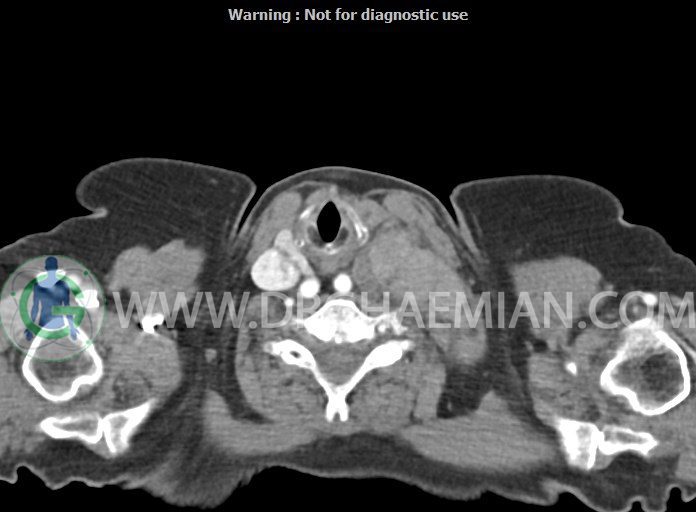

در سی تی اسکن اسپیرال از گردن با تزریق (مولتی دیدکتور 16 با مقاطع ظریف و بازسازی های ساژیتال و کرونال):

– تصویر توه های نسج نرمی oval shape متعدد با Enhancement تقریباً هوموژن، قرار گرفته در سمت چپ گردن، در لول غضروف کریکوئید با اثر فشاری شدید و compression ورید ژوگولار، با گسترش تحتانی به اینفراکلاویکولار چپ، به حداکثر ابعاد 28x50mm (با Enhancement مختصر هتروژن در این توده)

در درجه اول مطرح کننده لنفادنوپاتی متاستاتیک مطرح می باشد بالین، تومورهای منشأ گرفته از غلاف عصبی زنحیره سمپاتیک چپ گردنی، شبکه براکیال و لنفوم نیز در DDX قرار دارند. لذا نمونه برداری بافتی جهت بررسی بیشتر توصیه می شود.

– اسکولیوز مهره های سرویکال با تحدب به راست، احتمالاً در زمینه اثر فشاری توده های مذکور

مشهود است.